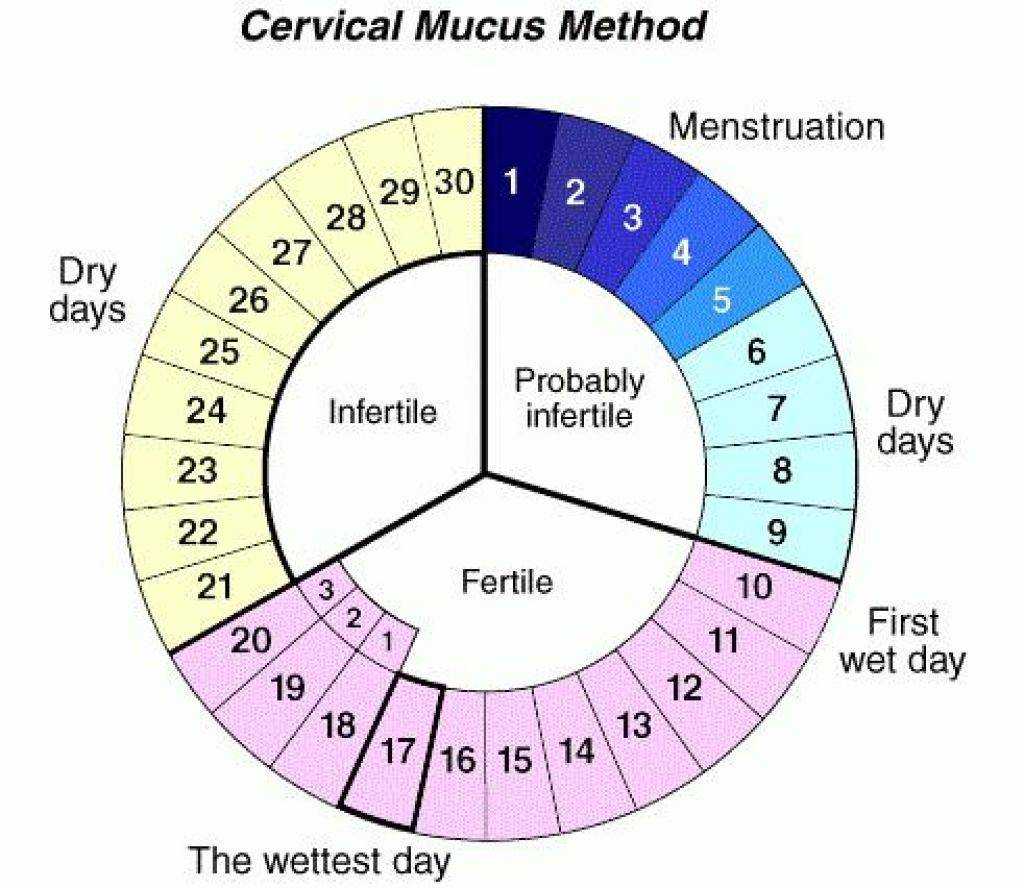

Рекомендации по зачатии